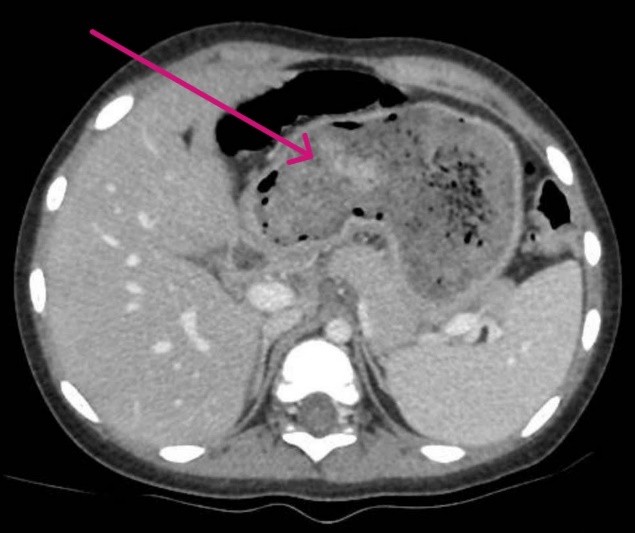

Qua thăm khám và chụp CT-scan, các bác sĩ phát hiện một búi tóc chiếm gần như toàn bộ dạ dày và kéo dài qua tá tràng xuống ruột non. Đây là biểu hiện điển hình của trichobezoar (búi tóc trong dạ dày) tiến triển thành hội chứng Rapunzel. Em A. được chỉ định phẫu thuật mở dạ dày để lấy búi tóc ra ngoài.

Hình ảnh scan búi tóc